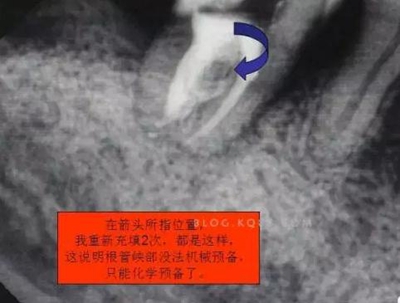

3.開(kāi)髓去腐后,髓腔基本就是這樣,在頰側(cè)近遠(yuǎn)中都有根管口顯示,初步用8號(hào)C+銼去試探性探查根管,沒(méi)有阻力感,以為就是c型根管,舌側(cè)用C+銼時(shí)有阻力感覺(jué),接上測(cè)量?jī)x去探查根管,以防C+銼探通后超出根尖孔,最后舌根長(zhǎng)度16mm*15號(hào)K銼(16.5mm*8號(hào)C+銼),機(jī)擴(kuò)F2。接下來(lái)著重頰側(cè)的根管尋找,后來(lái)在頰側(cè)近遠(yuǎn)中插入K銼時(shí)總覺(jué)得K銼尖段都指向一個(gè)位置,感覺(jué)不對(duì),再次讀X線片,后來(lái)發(fā)現(xiàn)術(shù)前沒(méi)有仔細(xì)查看X線片,以及未回顧這位患者年齡,也就忘記牙齒的增齡性改變的含義。髓腔之所以小或者不清楚,一個(gè)因?yàn)槟挲g增加的原因二是因?yàn)檠例X長(zhǎng)期受到外界物理化學(xué)刺激所導(dǎo)致髓腔變小,甚至沒(méi)有髓腔顯影。本病例患者,髓腔有大概顯影,但髓室里好像有增生的牙體組織,其實(shí)就是髓石。并且和髓室底相連接。如果不注意,有可能按常規(guī)預(yù)備方法進(jìn)行預(yù)備。

4.接著與患者溝通后,同意繼續(xù)去除髓石,用細(xì)小的安全端金剛砂車針輕微的去除,沿著弧形方向切割,去除后發(fā)現(xiàn)不是2個(gè)根管口,而是一個(gè)根管口,有點(diǎn)類似下頜6遠(yuǎn)中根管口的樣子。(遠(yuǎn)中頰根16mm*15號(hào)K銼)